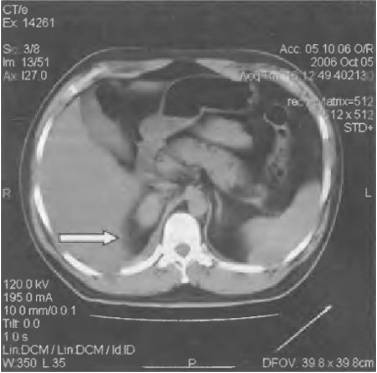

- КТ;

- компьютерной томографии;

- КТ и МРТ;

Диагностировать заболевание можно при помощи анализа крови, УЗИ почек, экскреторной урографии, КТ и МРТ.

Среди инструментальных диагностических методов используют УЗИ органов системы мочевыделения, экскреторную урографию, радиоизотопную ренографию, КТ и биопсию почек.

- компьютерную томографию;